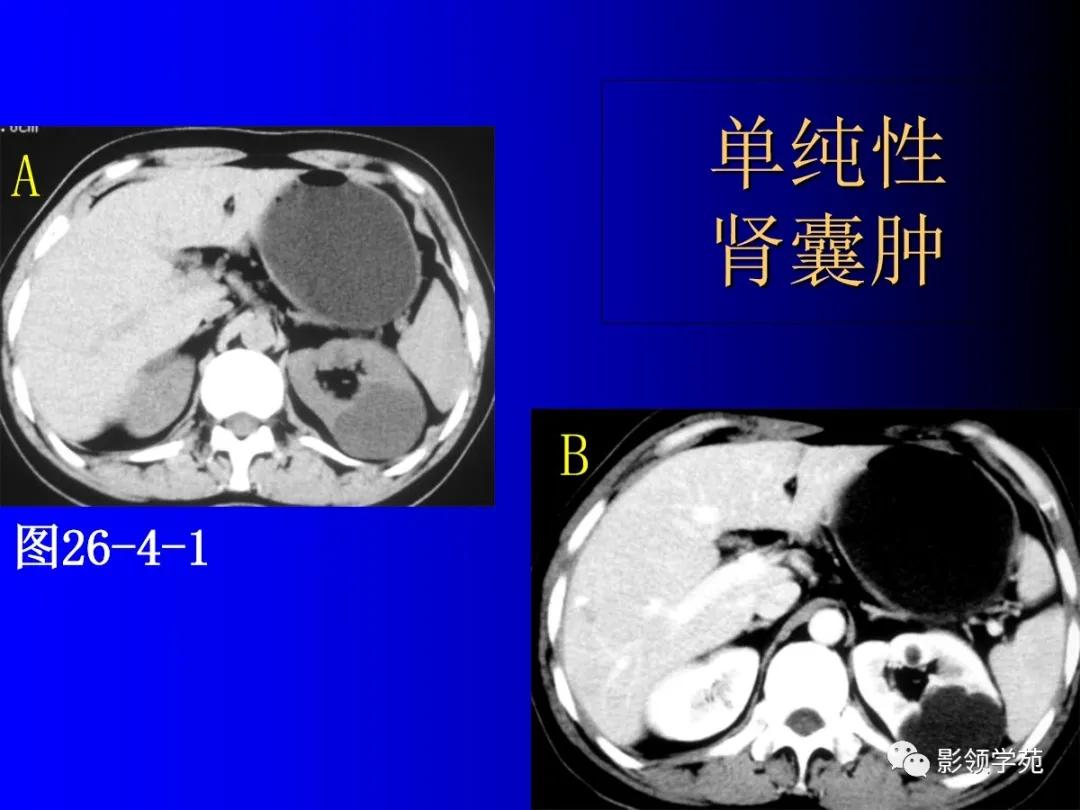

1、单纯性肾囊肿

位于肾皮质内的良性囊性病变。

常多发,大小不一。

呈圆形,壁菲薄光整,内衬扁平上皮,含清亮浆液。

囊肿可位于肾内或突出于肾轮廓外。

增强扫描无强化。